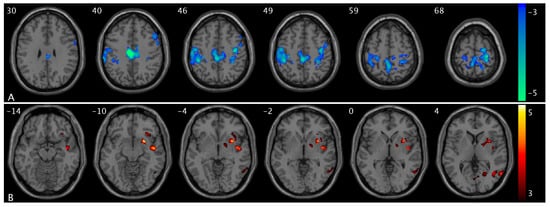

Compared to OAB participants at baseline, those at posttreatment demonstrated a significant increase in ΔPCC FC (from low to high urge) in the postcentral and parietal (PocP) regions (Figure 6). A summary of the cluster statistics is reported in Table S1. Post hoc regional analyses confirmed significant interactions between group and urge states. As urge states increased from low to high, the control group showed a significant increase in CBF in the mPFC region, whereas the OAB group exhibited no change (Figure 7A). In the supramarginal region, the control group displayed a significant decrease in CBF with rising urge states, while the OAB group displayed a significant increase (Figure 7B). The control group demonstrated a significant increase in PCC-insula FC as urge states rose, while the OAB group showed a significant increase in PCC-insula FC (Figure 7C). ΔCBF values in the mPFC from low- to high-urge states were significantly correlated with anxiety scores (p = 0.0043), while ΔFC scores between the PCC and insula were significantly correlated with depression scores (p = 0.0059). However, no significant associations were found between ΔCBF or ΔFC and age (p > 0.05). Notably, the group-by-urge interaction effects remained unchanged after adjusting for age and anxiety/depression. Furthermore, we showed changes in PCC-PocP FC with increasing urge levels for the control and OAB groups because of the interaction between treatment and urge states. Both the control and OAB groups exhibited significant decreases in PCC-PocP FC (Figure 7D) as urge states increased. At baseline, the OAB group exhibited a significant decrease in PCC-PocP FC, but posttreatment, the group showed a significant increase in PCC-PocP FC as urge states intensified (Figure 8A). Since bladder volumes at maximum capacity were significantly larger posttreatment, we consider bladder volume a treatment-related symptom measure for OAB. We found that the OAB participants with improved symptoms (increased bladder volumes posttreatment) experienced smaller increases in ΔPCC-PocP FC (from low- and high-urge states) (Figure 8B).

Figure 6. Statistical maps overlaid on T1-weighted images showing treatment effect. Increases in ΔPCC FC (from low- to high-urge state) in the postcentral and parietal regions in OAB/posttreatment compared to OAB/baseline. The numbers in the top left corner of the MRI images indicate the z-coordinate (in mm) in the MNI space. The color bar represents t-values.